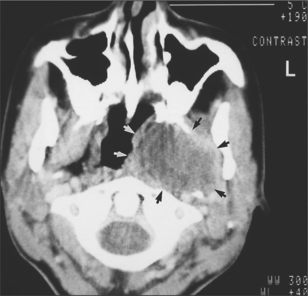

Another presentation of salivary gland disease in HIV-positive patients is multiple parotid cysts causing gross parotid swelling and significant facial disfigurement. On imaging with CT or MRI the parotids have the appearance of a Swiss cheese, with multiple large cystic lesions (Fig. 14.4). The glands are not painful and there is no reduction in salivary flow rate. Surgery may be indicated to improve the appearance.

image

Fig. 14.4 This MRI scan shows the typical ‘Swiss-cheese’ appearance of multiple large cysts within the parotid glands.